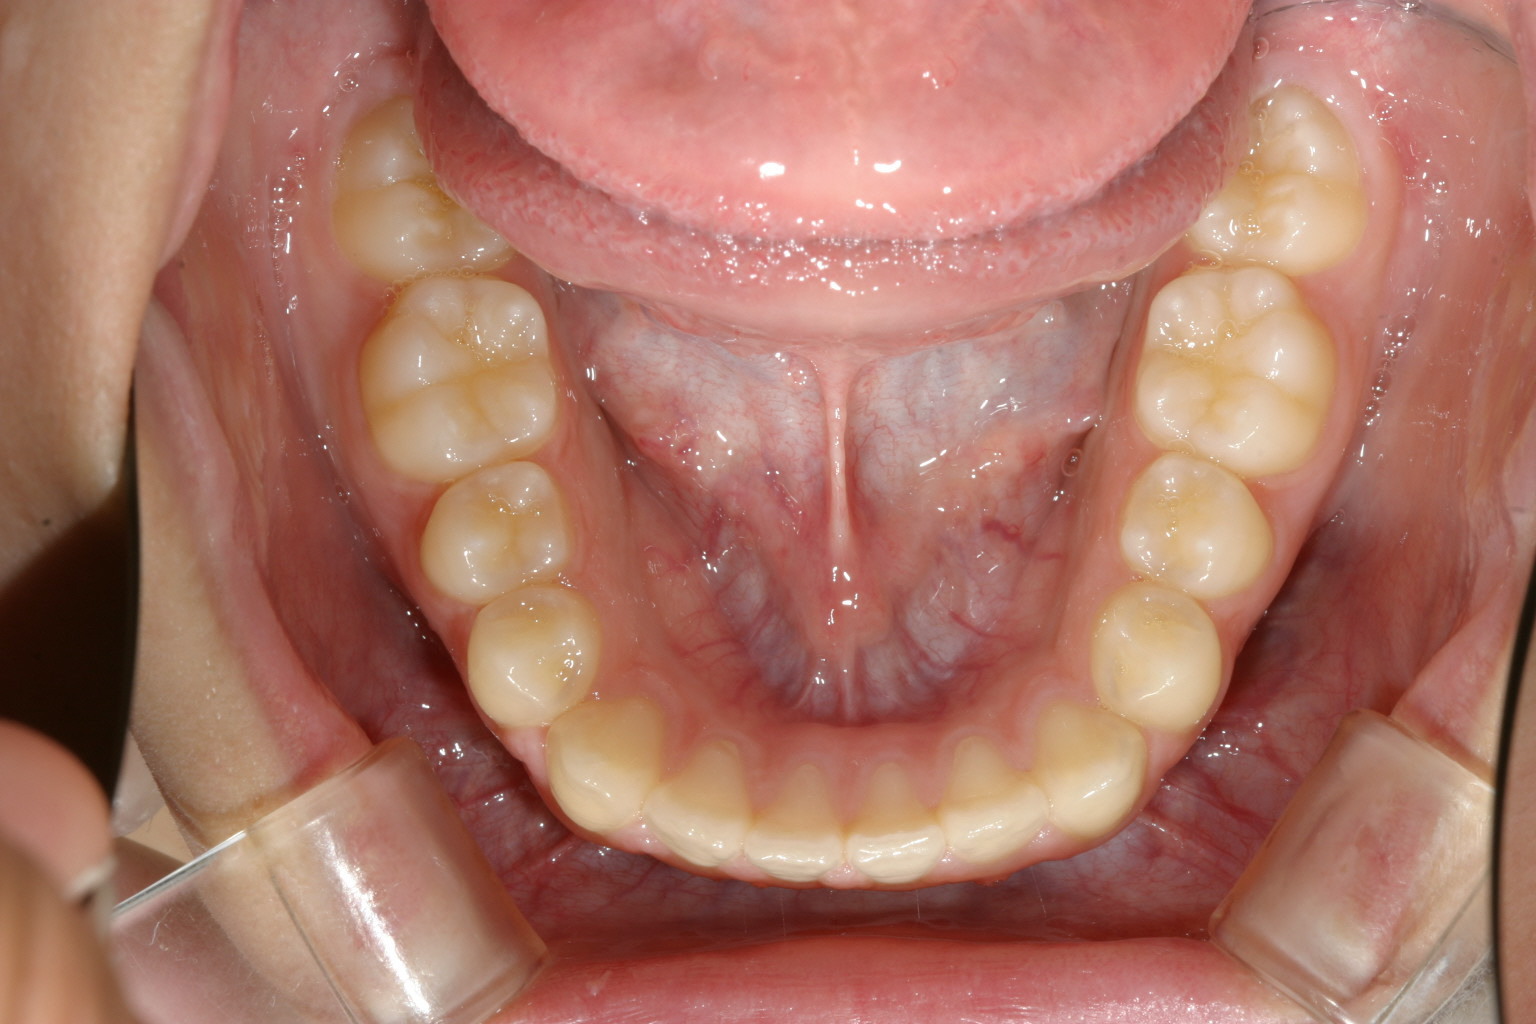

下顎の歯列は全然問題ないです。

下顎は問題なしです。